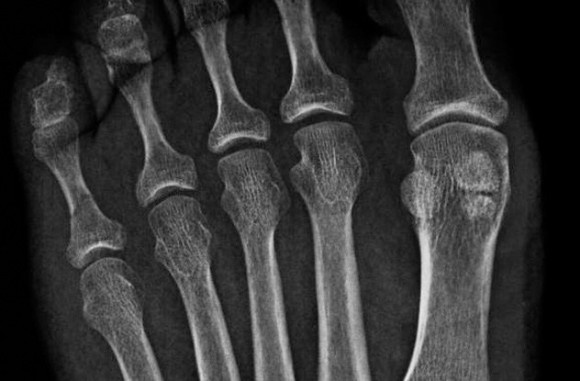

■ 2. 人間とコアラの指紋

ゴリラなどの霊長類にも人間と同じ指紋があることはよく知られているが、実はあのコアラにもある。これは何かを掴むときに便利だ。もちろん霊長類特有の行動で、他の種は基本的にやらないことである。コアラは進化上、霊長類とは何ら関連がないが、人間そっくりな指紋がある。霊長類とコアラの祖先である有袋類が系統樹から分かれたのはおよそ7,000万年前のこと。以来、他の有袋類に指紋はない。つまりコアラが最近になってこれを手に入れた可能性が高いことを物語っている。

コアラと人間の指紋は、犯罪捜査の専門家ですら困惑させるほど似ているのだから驚きだ。